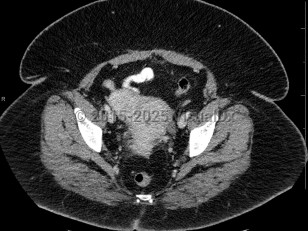

Uterine fibroidsUterine fibroids

EndometriosisEndometriosis

Ovarian cancerOvarian cancer